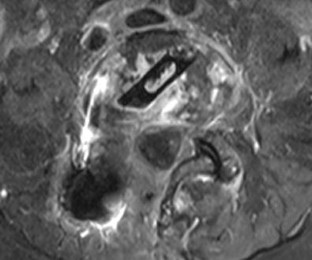

Fig. 1

Fig. 2

Fig. 3

Fig. 4

Fig. 5

Fig. 6

Fig. 7